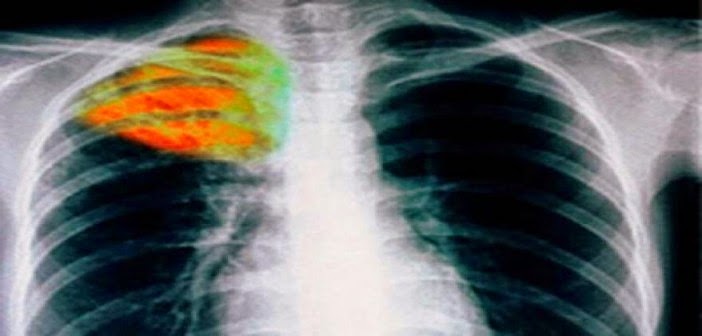

24 Μαρτίου Παγκόσμια Ημέρα Φυματίωσης

Στις 24 Μαρτίου του 1882 ο Robert Koch ανακοίνωσε την ανακάλυψη του αιτίου της φυματίωσης. Σε ανάμνηση λοιπόν εκείνης της ημέρας, η 24η Μαρτίου καθιερώθηκε από τoν Παγκόσμιο Οργανισμό Υγείας και τη Διεθνή Ένωση κατά της Φυματίωσης και των Νόσων του Αναπνευστικού Συστήματος ως Παγκόσμια Ημέρα Φυματίωσης. Η καθιέρωση αυτή αποσκοπεί στην ενημέρωση, στην ευαισθητοποίηση και στην ανάληψη δράσεως κατά της φυματίωσης σε παγκόσμιο επίπεδο.